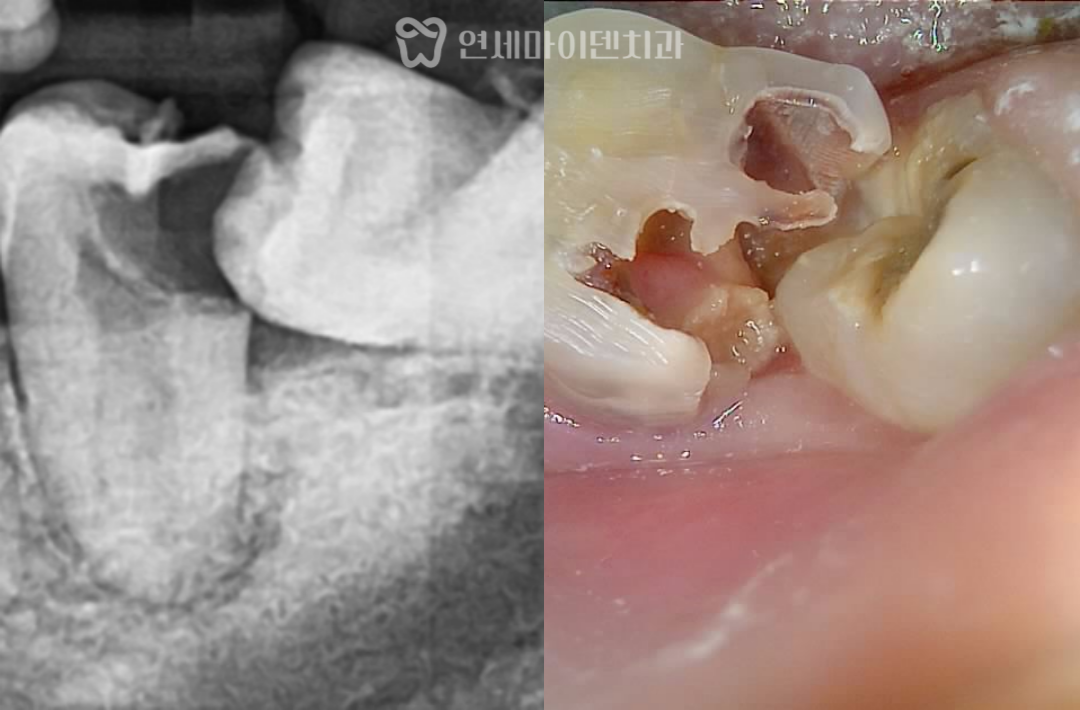

방사선 사진에서 확인해 보면

사랑니가 정상적으로 올라오지 못하고

앞쪽 어금니 방향으로 누워 있는 상태였습니다.

이번 케이스에서도

사랑니와 맞닿아 있는 앞 어금니가

이미 깊게 썩어 있는 상태였습니다.

충치를 제거해보니

치아의 절반 이상이 손상된 상태였고,

잇몸이 안쪽으로 말려 들어가 있어

치료 과정 중 출혈도 많은 상황이었습니다.

그럼에도 불구하고

치아 뿌리 상태는 비교적 유지되어 있었고,

남아 있는 치질이 약 50% 정도 확인되어